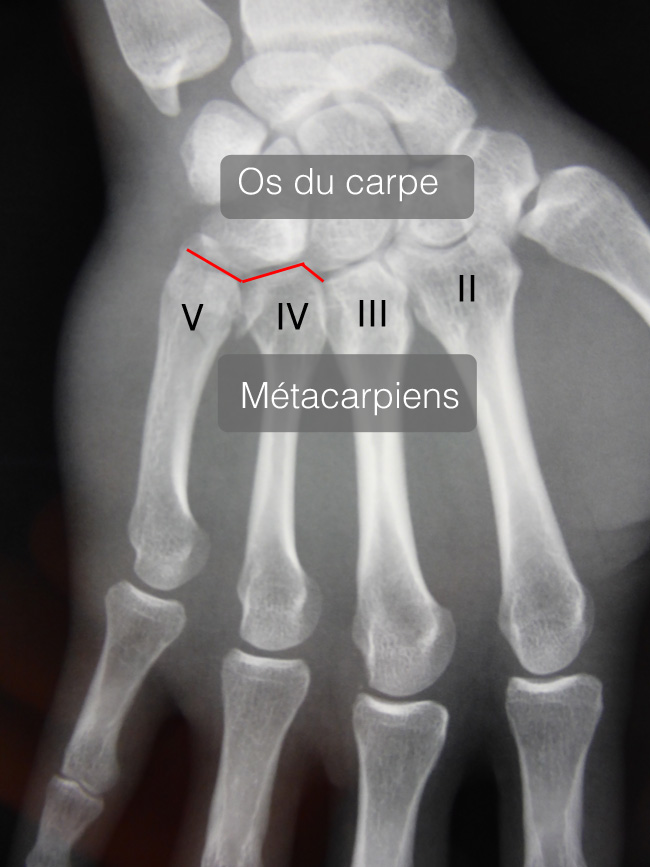

Les articulations carpométacarpiennes relient le poignet avec la main. Sur le plan anatomique, ce sont des articulations entre les os du carpe et la base des métacarpiens.

Les articulations des 5 eme et 4 eme métacarpiens sont de loin les plus souvent atteintes et les plus graves.

Les articulations des 2 eme et 3 eme métacarpiens sont très rares et posent peu de problèmes.

La fracture passe souvent inaperçue par l’examen de la main aux urgences et seule la radiographie et le scanner peuvent faire le diagnostic.

Il est important de préciser combien de métacarpiens sont atteints et s’il s’agit de fractures simples, fractures articulaires ou fractures luxations.

Les radiographies ne suffisent pas à un diagnostic précis.

Seul le scanner permet un examen détaillé.